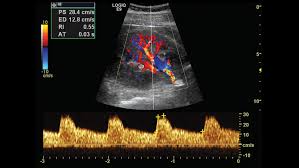

Doppler Ultrasound Of The Kidneys Ultrasound Vascular Ultrasound Ultrasound Sonography

A renal artery doppler test is a type of ultrasound that measures the speed of blood flow in the arteries leading to the kidney explains webmd.

The flank approach is practical for visualizing the mid and distal renal arteries more than the proximal renal artery. The central approach of renal transplant ultrasound is to evaluate for possibly treatable surgical or medical complications arising in the transplanted kidney. Any vessels identified must be traced to the kidney to confirm their identity. A renal artery doppler test is a type of ultrasound that measures the speed of blood flow in the arteries leading to the kidney explains webmd.